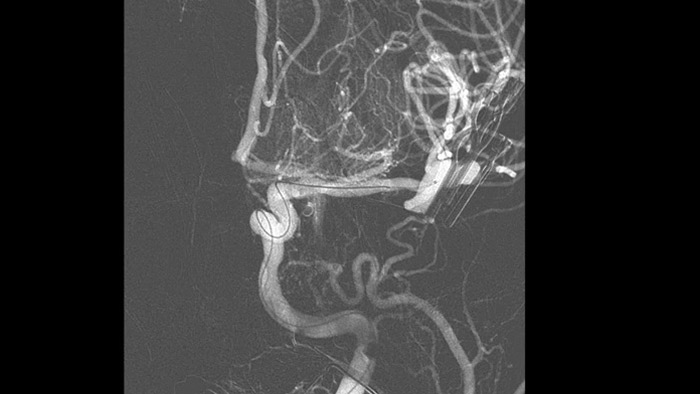

O MR-CT Roadmap oferece a possibilidade de sobrepor um exame de SmartCT Angio ou Angio de RM previamente adquirido com fluoroscopia em tempo real para visualizar os limites da lesão e a vascularização correspondente para avaliação de risco. A reutilização de dados pré-adquiridos ajuda-o a gerir a dose de raios X e o meio de contraste.

Melhorar a visualização de stents endovasculares, flow diverters e outros dispositivos, bem como a morfologia do vaso até o nível de perfurador com SmartCT Vaso. Esta técnica de aquisição baseia-se num exame de TC de feixe cónico e numa injeção de contraste intra-arterial. É cada vez mais utilizada para o acompanhamento de aneurismas tratados com stents de flow diverter para verificar o posicionamento do dispositivo.

O SmartCT Roadmap melhora a visualização de vasos sobrepostos para suportar uma navegação precisa do fio-guia e do cateter através do sistema vascular complexo. Oferece uma precisão de alto nível com compensação em tempo real para pequenos movimentos da gantry, da mesa e dos pacientes.

O Roadmap Pro é um mapa avançado de duplo contraste que ajuda a melhorar a visibilidade dos vasos sobrepostos enquanto equilibra a exposição às radiações. Pode ser personalizado para mostrar o avanço durante a colocação da bobina.